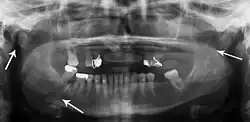

multiple mandible fractures of a patient in the right condyle (extracapsular/neck/not dislocated), right body (vertically unfavourable) and left coronoid process